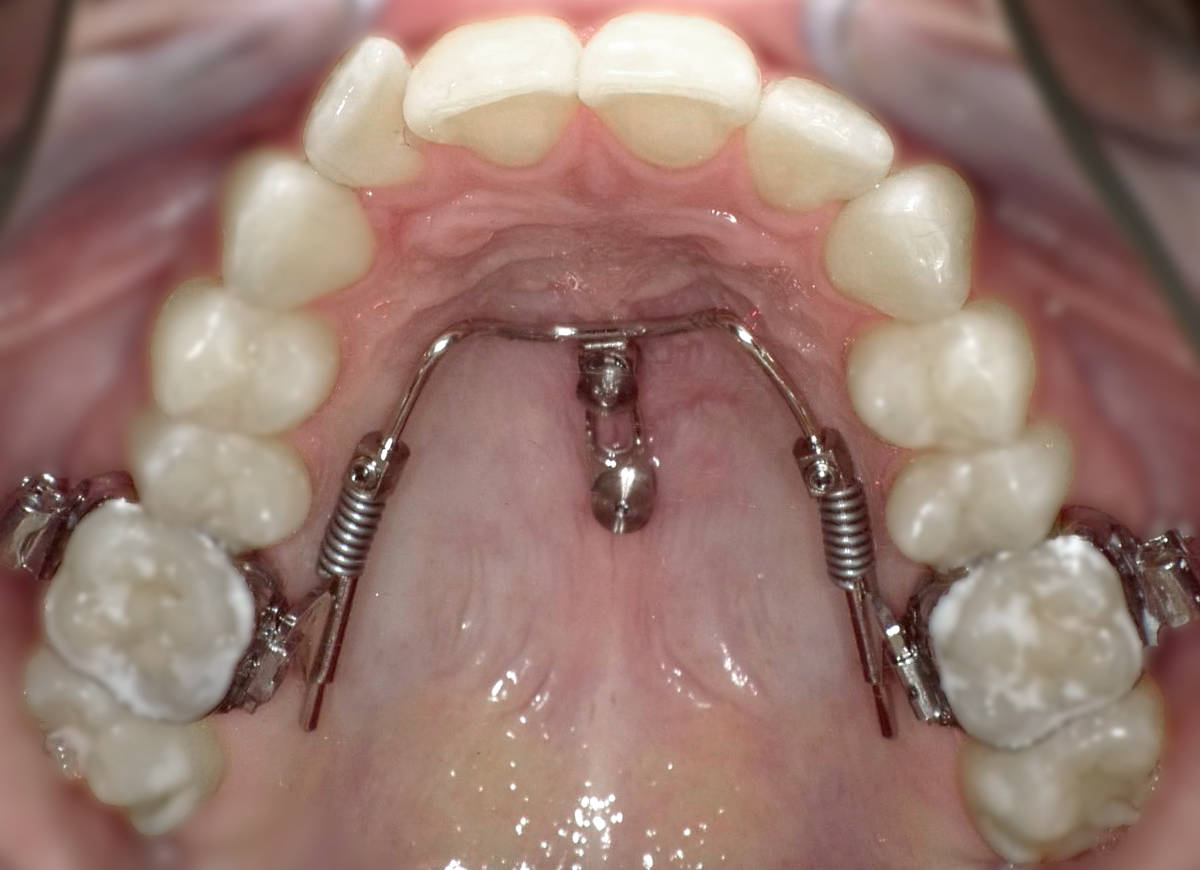

Bei PINs (engl. “Stift“) handelt es sich um Minischrauben, die unter örtlicher Betäubung der Mundschleimhaut im Kieferknochen befestigt werden. Dadurch lassen sich zum Beispiel Apparaturen mit Außenbögen (Headgear) vermeiden, da im Mund mit Hilfe der PINs mehr Verankerungsmöglichkeiten geschaffen werden. Kleine Zug- oder Druckfedern oder kieferorthopädische Drähte können daran befestigt und mit der Zahnspange verankert werden.

PINs werden übrigens auch TADs (Temporary Anchorage Device) genannt, denn sie bleiben nur für eine bestimmte Zeit im Mund und werden dann wieder entfernt.